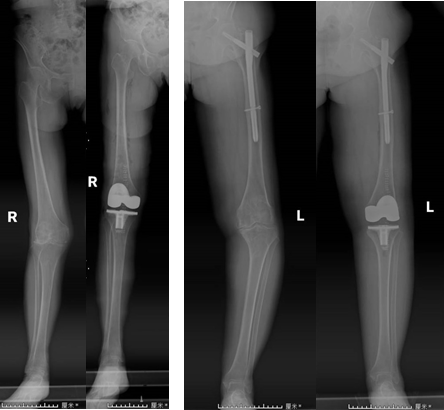

手術前后患者X線片對比

膝關節(jié)疼痛是困擾老年人常見的問題,而膝關節(jié)置換手術是治療終末期膝關節(jié)退變的主要有效手段。近日,我院關節(jié)運動醫(yī)學科康立新主任醫(yī)師團隊,利用全膝關節(jié)手術定位系統(tǒng)(iKAPS)完成兩例復雜膝關節(jié)置換手術。該技術為膝關節(jié)畸形嚴重、股骨髓腔閉鎖或者既往股骨近端手術有內(nèi)植物的患者進行膝關節(jié)置換,提供了一種更加精準、有效的治療方法。

術中使用類似麻將牌大小的下肢力線測量儀,配合醫(yī)療交互軟件和配套工具,精準地測量出股骨遠端和脛骨平臺的截骨角度,輔助手術者進行個體化的精準截骨,恢復下肢力線。術中不需要打開股骨髓腔,比傳統(tǒng)手術出血少、恢復快。

全膝關節(jié)手術定位系統(tǒng)(iKPAS)可用于初次或復雜全膝關節(jié)置換手術,在不開髓的情況下實現(xiàn)膝關節(jié)力線的定位,尤其針對股骨骨折內(nèi)固定物未取出的情況,優(yōu)勢更加明顯。